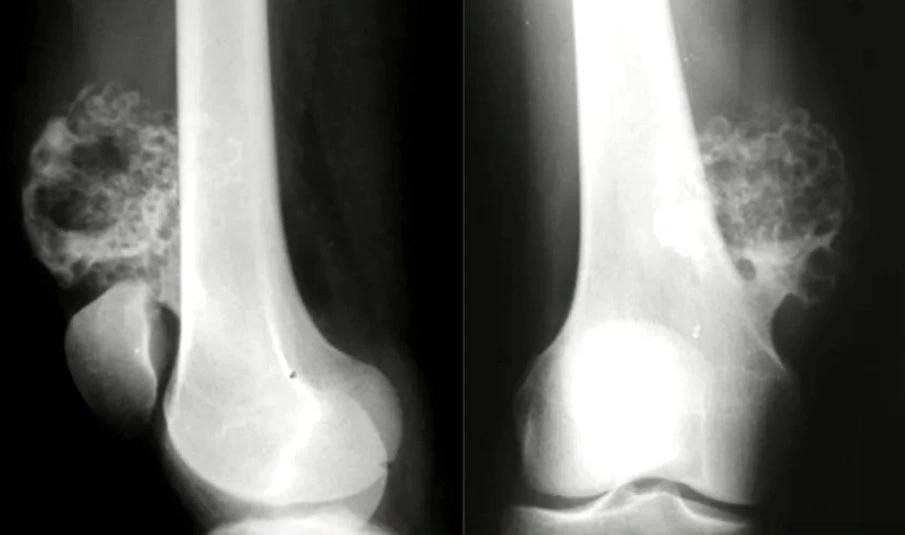

التصوير الشعاعي

يجري الطبيب تصويرًا بالأشعة السينية في بداية الأمر وذلك لإنتاج صورة كاملة للعظام، بالإضافة إلى التصوير بالرنين المغناطيسي الذي يتم باستخدام مزيج من المغناطيسات الكبيرة والترددات الراديوية وجهاز كمبيوتر؛ لإنتاج صورة مفصّلة وشاملة للأعضاء والأنسجة الرخوة والعضلات والأربطة وهياكل أخرى من الجسم، وجدير بالذكر أنّ الطفل لا يتعرض عند التصوير بالرنين المغناطيسي لأي إشعاع.